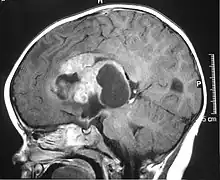

IRM d'une tumeur tératoïde rhabdoïde atypique.